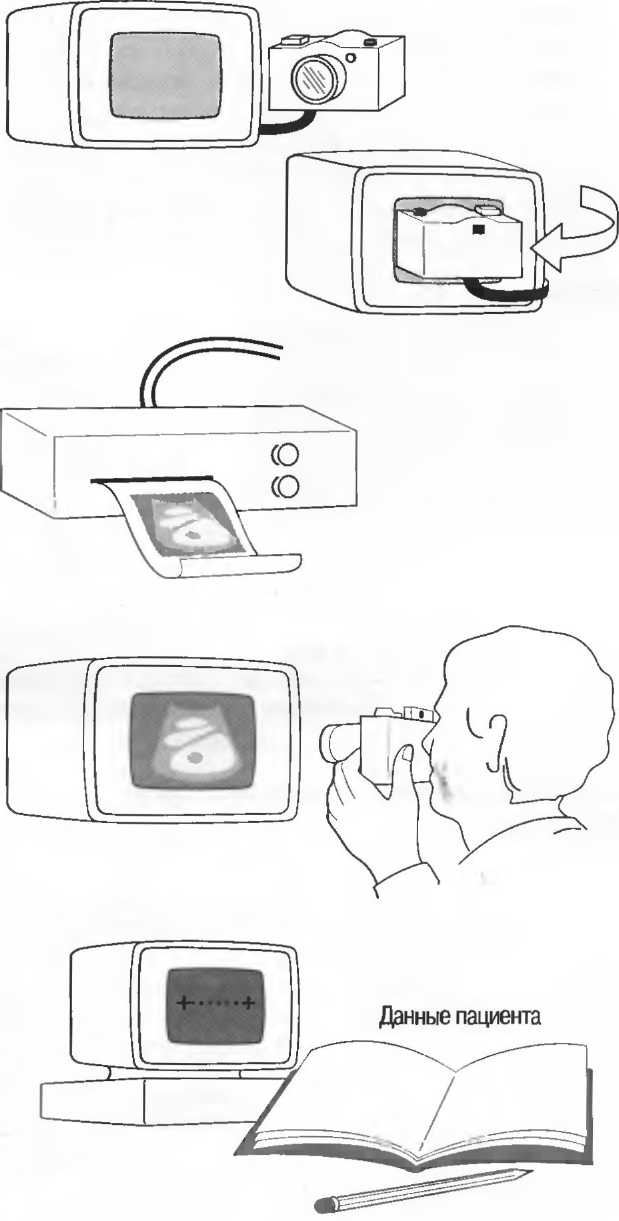

Регистрация изображения

Необходимо, чтобы была возможность добавлять к изображению идентификационные и другие данные пациента: крайне желательно, чтобы наиболее важные эхограммы фиксировались в истории болезни пациента. Есть несколько способов, различных по стоимости и эффективности, сделать это.

1. Наилучший и наиболее дорогой способ — это регистрация изображения на рентгеновской пленке. Для этого необходимы регистрирующее изображение, устройство и специальная камера. Также необходима темная комната. Может использоваться обычная рентгеновская пленка, но наилучшие результаты получаются на специальной односторонней рентгеновской пленке, стоимость которой достаточно высока. Менее дорогой является печать на бумаге, однако ее качество ниже (см. пункт 3, ниже).

2. Следующий метод также дорог: он требует наличия регистрирующей камеры и пленки специально для ультразвукового оборудования. И камера, и пленка достаточно дороги и не всегда доступны. Тем не менее качество высокое, и фотографии можно получить практически сразу.

3. Есть устройство, регистрирующее изображение на специальной бумаге (это значительно дешевле, чем использование пленки). Получаемые эхограммы достаточны по качеству для обычных исследований, но необходимо защищать бумагу от перегревания и света.

4. Изображение на экране может быть сфотографировано на обычной черно-белой пленке с использованием 35-миллиметровой камеры. Необходимо наличие линз для съемки с близкого расстояния. Пленка проявляется и печатается обычным путем. Это требует времени, особенно в условиях сельской больницы.

5. Если нет возможности приобрести регистрирующее устройство, то все точные детали и необходимые измерения должны быть зарегистрированы в протоколе обследования пациента.

Нельзя полагаться только на собственную память.